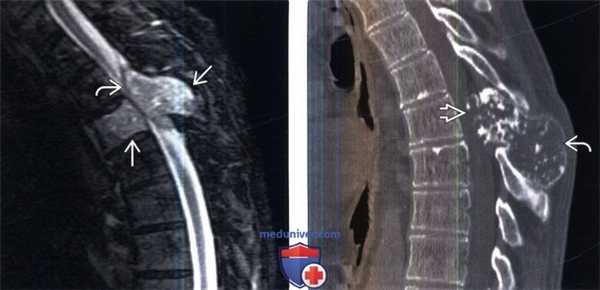

(Слева) Сагиттальный срез, STIR МР-И: образование, поражающее остистый отросток и тело верхнего грудного позвонка. Эпидуральный компонент опухоли сдавливает дуральный мешок и спинной мозг. МРТ не позволяет адекватно оценить минерализацию опухоли, поэтому картина опухоли выглядит достаточно неспецифично.

(Справа) Сагиттальный КТ-срез (этот же пациент): также визуализируется экспансивное объемное образование, полностью замещающее собой остистый отросток пораженного позвонка. Увеличение объема дорзальной части дуги позвонка стало причиной выраженного стеноза спинномозгового канала.